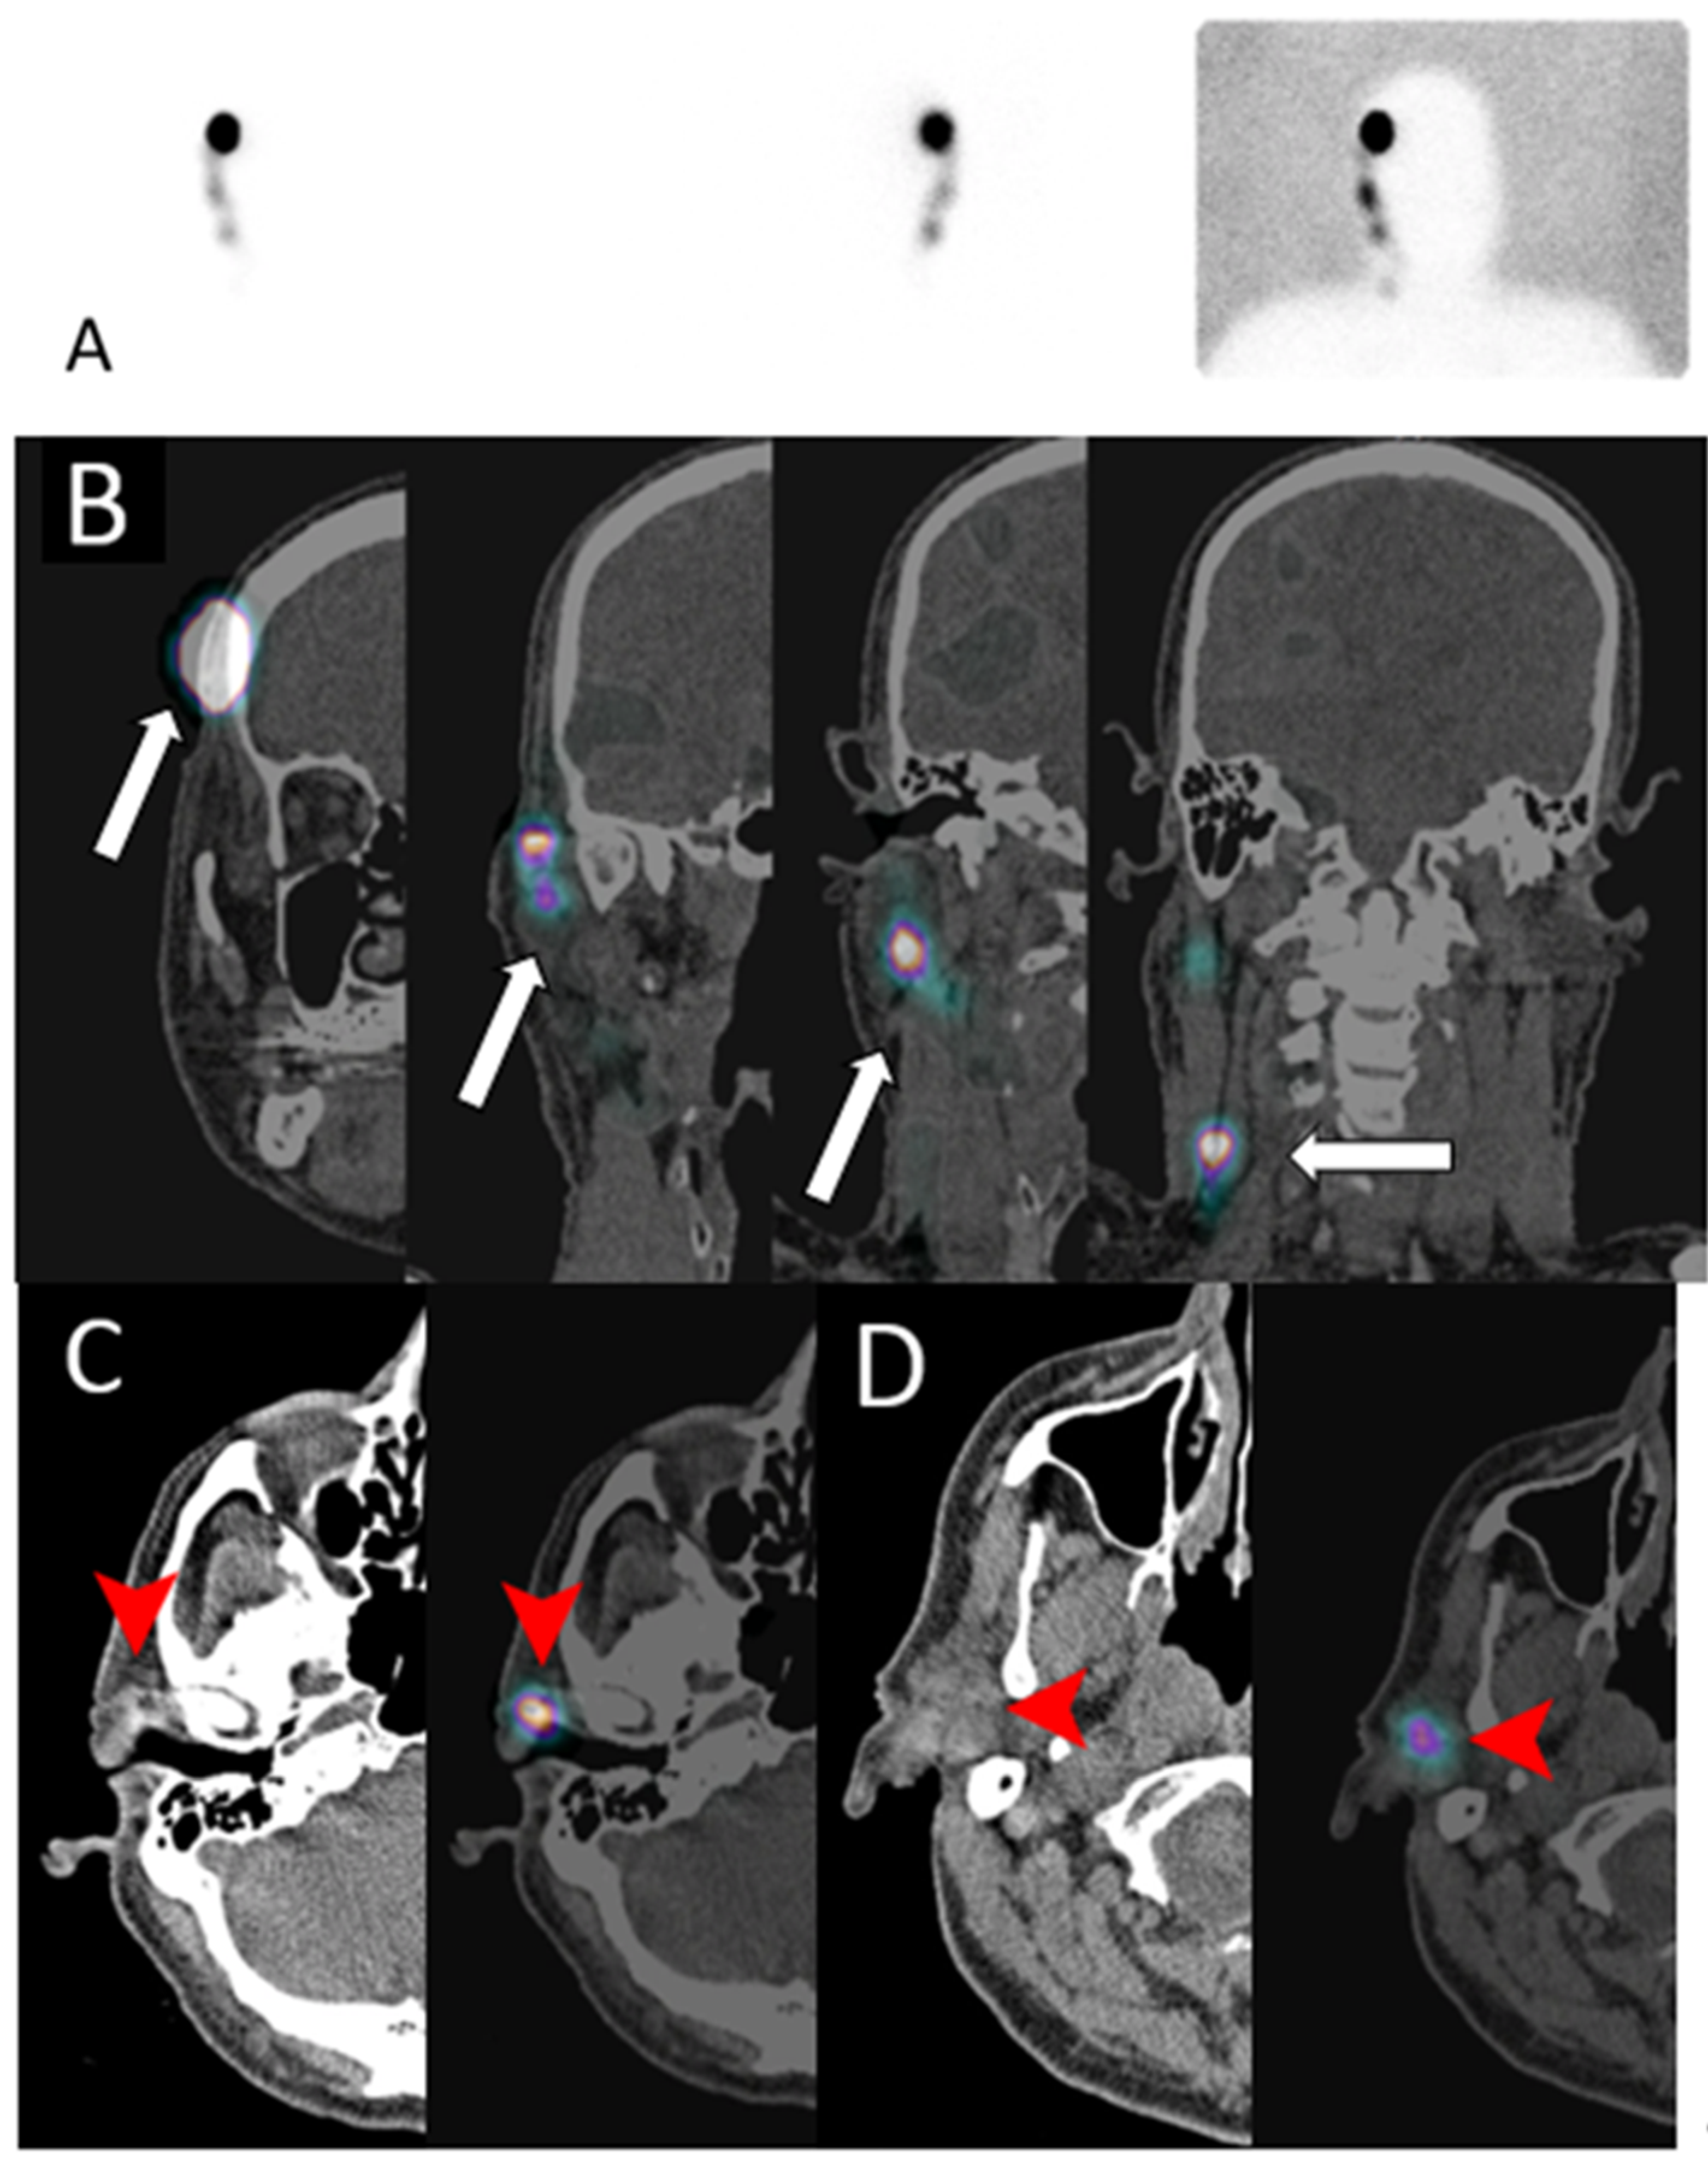

Lymphoscintigraphy

- Skanjeti, A.; Dhomps, A.; Paschetta, C.; Tordo, J.; Bolton, R.C.D.; Giammarile, F. Lymphoscintigraphy for Sentinel Node Mapping in Head and Neck Cancer. Semin. Nucl. Med. 2021, 51, 39–49. [Google Scholar] [CrossRef]

- Quartuccio, N.; Garau, M.L.; Arnone, A.; Pappalardo, M.; Rubello, D.; Arnone, G.; Manca, G. Comparison of 99m TC-Labeled Colloid SPECT/CT and Planar Lymphoscintigraphy in Sentinel Lymph Node Detection in Patients with Melanoma: A Meta-Analysis. J. Clin. Med. 2020, 9, 1680. [Google Scholar] [CrossRef] [PubMed]

- Kwak, J.J.; Kesner, A.L.; Gleisner, A.; Jensen, A.; Friedman, C.; McCarter, M.D.; Koo, P.J.; Morgan, R.; Kounalakis, N. Utility of Quantitative SPECT/CT Lymphoscintigraphy in Guiding Sentinel Lymph Node Biopsy in Head and Neck Melanoma. Ann. Surg. Oncol. 2019, 27, 1432–1438. [Google Scholar] [CrossRef] [PubMed]